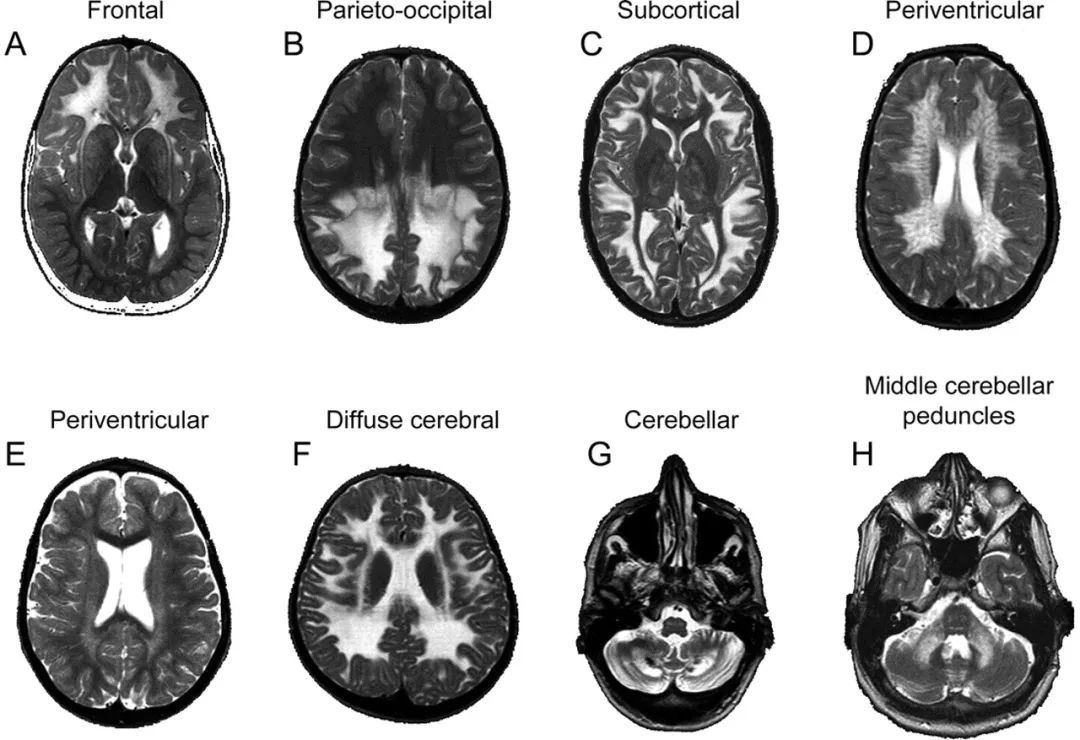

(2)遗传性疾病

➤ 如异染性脑白质营养不良及肾上腺脑白质营养不良;

➤ 脑白质弥漫性、对称性白质高信号;

➤ 临床一般为儿童、轻壮年。

➤ 从影像上看:

额优势:亚历山大病,

室周优势:异染性脑白质营养不良,

顶枕优势:克拉伯病,

弥漫性脑:伴有皮质下囊肿的巨脑脑白质病(MLC),

后颅窝优势:脑腱黄瘤病(见下图)。